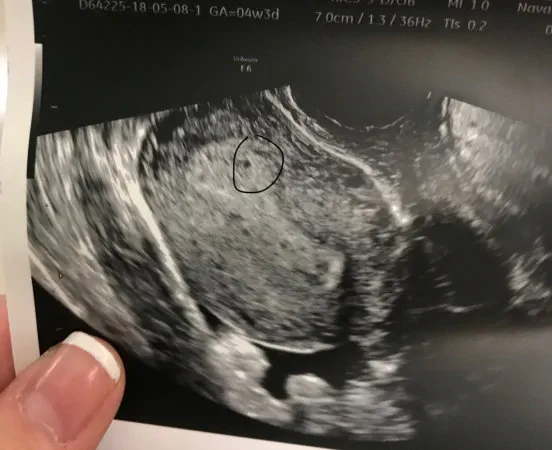

El establecimiento probablemente ocurrió hace unos días. Las cosas toman tiempo para desarrollarse. Es por eso que el ultrasonido generalmente no se realiza antes de las 8 semanas, no hay nada que hacer.

Es absurdamente temprano para la ecografía. Todo lo que esperas ver es un forro grueso. Ver todas las respuestas (1) - Póster original Daxy dijo: Sí, esto es normal.

El establecimiento probablemente ocurrió en un entero Fe ... El mío no parece demasiado pequeño durante 4 semanas 3 días, ¿verdad? Ver todas las respuestas (1) - Póster original Potvskettle dijo: Es absurdamente temprano para la ecografía. Todo lo que esperas ver es ... Nunca volveré a tener el comienzo de un escaneo ... teme que nada haya perdido a un bebé. Ver todas las respuestas (1)

BabyJanaury2019 dijo: El mío no parece demasiado pequeño durante 4 semanas 3 días, ¿verdad? Se ve muy bien. - Había hecho una a 4 semanas y 5 días y no vi nada y mi Dr. dijo que puede ser ectópico Ver todas las respuestas (1)

Acabo de tener un ultrasonido en 4 semanas también después de perder un bebé en septiembre debido a un ectópico. Querían verificar y ver si había algo en el tubo que me quedaba ... no había mucho que ver, solo un forro grueso. No me siento mejor al respecto